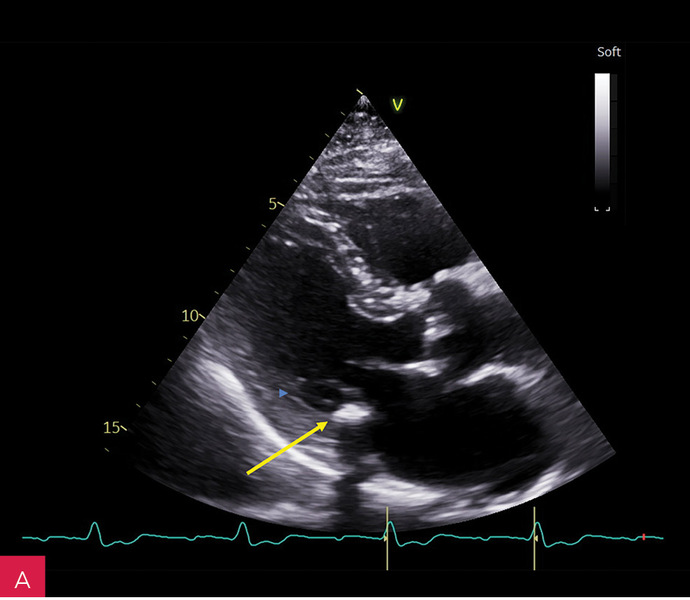

Rycina 5A-C. Badanie echokardiograficzne przezklatkowe dwuwymiarowe (2D TTE) w projekcji koniuszkowej czterojamowej. Znacznie powiększone przedsionki i niewielkie wymiary komór serca. W zależności od płaszczyzny przekroju w kierunku przód–tył (A, B, C) zmienia się uwidocznienie zmiany guzowatej – CCMA (serowate zwapnienie pierścienia mitralnego). Jest ona w pełni widoczna w zmodyfikowanej projekcji obrazującej struktury położone jak najdalej ku tyłowi serca (C)